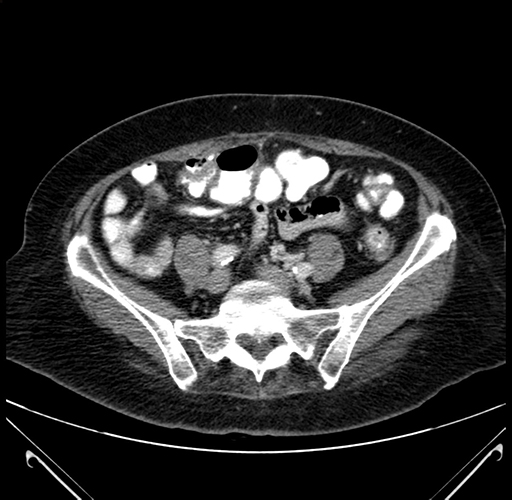

Axial Venous